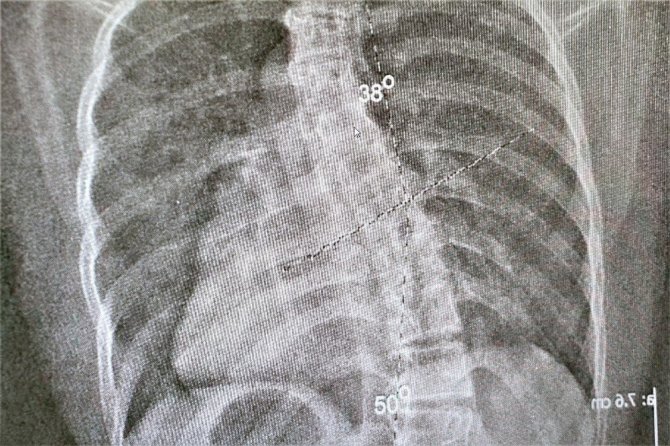

Skolyoz hastalığı ve belirtileri hakkında bilgi veren Fizyoterapist Muhammed Barış, " Skolyoz, omurgada üç boyutta meydana gelen eğrilmelerin oluşturduğu bir deformitedir. Çok net bir şekilde evde yapılabilecek basit testlerle bu hastalığın varlığını anlayabiliyoruz. En çok hitap ettiğimiz, lise ve ortaokul grubu çocuklardır. Çünkü bu yaşta fark edildiği zaman skolyozun tedavisinde daha etkin sonuçlar alabiliyoruz. Özellikle çıplak bir şekilde çocuğunuza arkadan baktığınız zaman kürek kemiklerinde biri diğerine oranla biraz daha aşağıda duruyorsa,omuz boylarında eşitsizlik varsa, daha aşağı geldiğimiz zaman kalçada da bir eşitsizlik varsa bizlere başvurmalarını öneriyoruz. Bize en çok "bir bacağım diğerine göre daha kısa hissediyorum,nefes alırken kaburgalarım bana batıyor,bir omuzum diğerine oranla daha aşağıda yada aynadan baktığımda iki tarafım eşit değil" gibi şikayetler ile geliyorlar. Bu şikayetlerle gelen hastalarımızı ilgili birimlerin uzman hekimlerine yönlendiriyoruz.Skolyoz tanıları alındıktan sonra fizik tedavi biriminde seanslarımıza başlıyoruz" dedi.

Skolyoz hastalığının istatistiksel verilerini paylaşan Barış" Yapılan çalışmalarda bu hastalık grubunda yüzde 2 ile 4 arasında bir oran var. Yani 100 kişiden 2'si veya 4'ü skolyoz hastası. Bunun büyük bir kısmı bu deformitenin farkında değil. Kız çocuklarında erkek çocuklarına oranla 8-10 kat daha fazla gözüküyor. Burada bizim için en önemli olan şey, kız çocuklarında menarj döneminde büyüme hormonu daha fazla salgıladığı için omurgada uzama meydana geliyor.Meydana gelen bu uzama mevcut skolyoz açısının artmasına sebebiyet veriyor. Skolyoz hastası bir kız çocuğunun mutlaka ilk reglinden hemen sonra bir fizyoterapiste danışması gerekiyor. Ondan sonraki 6 ay ile 2 senelik dönemde mutlaka kontrolümüzde olması gerekiyor" diye konuştu.